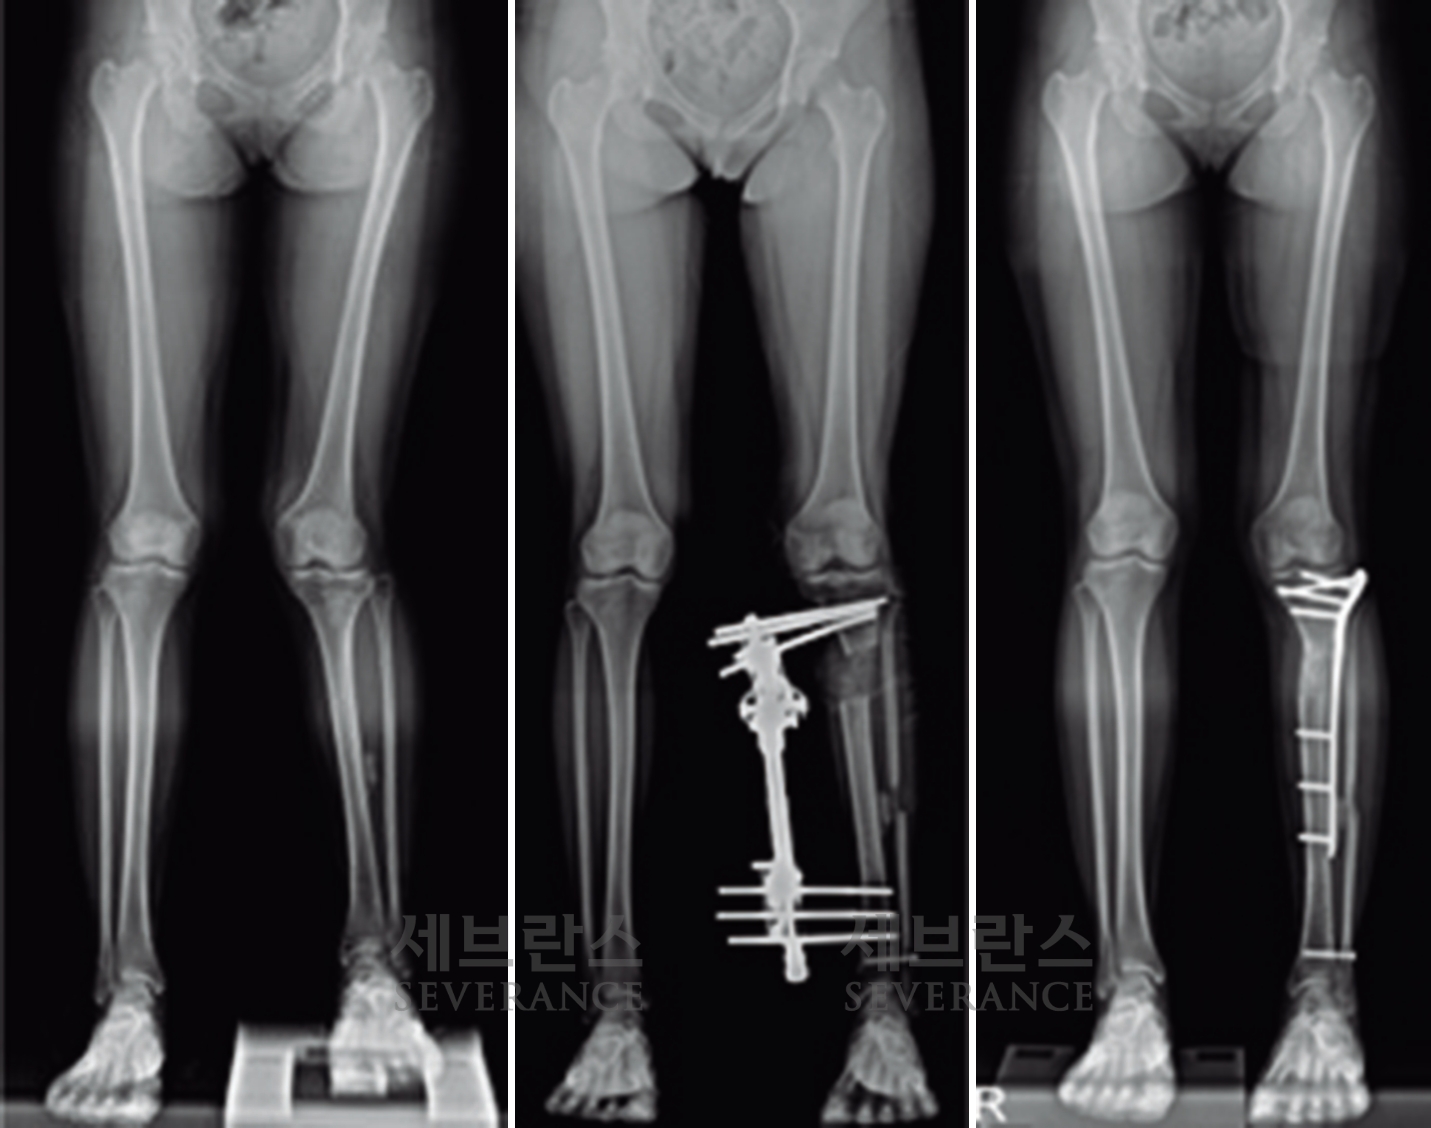

- 절골 교정술

성장이 끝난 환자나 변형이 심한 경우에는 절골 교정술이 효과적입니다. 이 수술은 뼈를 잘라 바른 위치로 되돌린 뒤 금속 장치로 고정하는 방식으로, 수술 직후 곧바로 교정 효과를 볼 수 있습니다. 그러나 절골된 뼈가 단단히 붙을 때까지 약 2-3개월이 소요되며, 그동안은 목발 보행 등 활동에 제약이 따릅니다.

구루병으로 발생한병적 내반슬(O다리) 변형에 대해

절골 교정술을 시행한 환아

성장판 손상으로 발생한 좌측 외반슬 및 하지부동에 대해 골연장술과 교정술을 동시에 시행해 치료한 환아